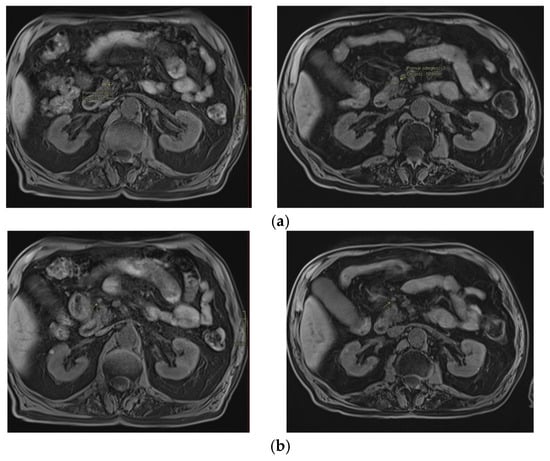

3. Second Case